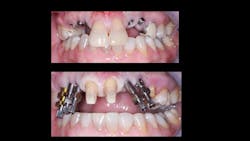

Improper implant placement. This is an extremely important factor. Placement of implants in locations where they receive abusive occlusion or excessive loading is inviting failure (figures 2–4).

Poorly designed prosthesis. Practitioners placing implants should have significant knowledge of prosthodontics. When implants are placed in incorrect locations, both proper loading of the implants and development of an optimal esthetic result are compromised.